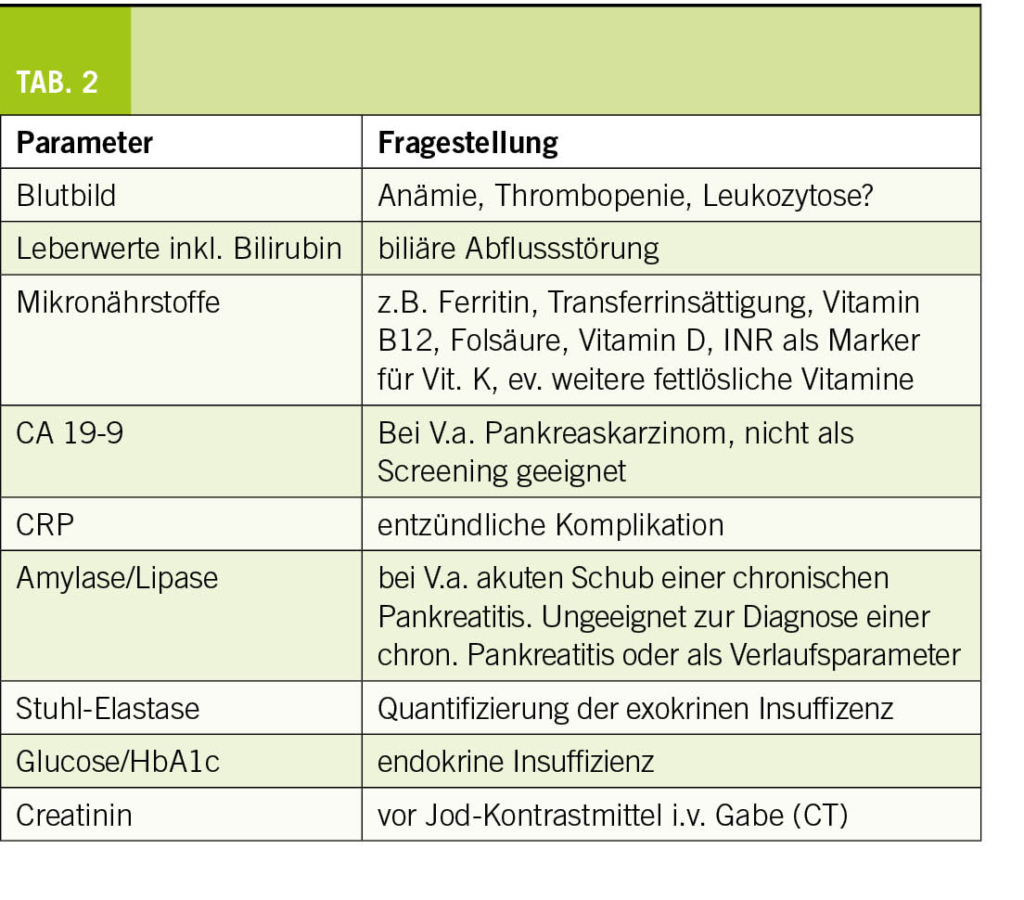

Bitte beachten Sie die Tabelle 2 mit den möglichen Laborparametern für eine Kontrolluntersuchung in der Praxis.

– je nach Klinik Laborkontrolle (Tab. 2)